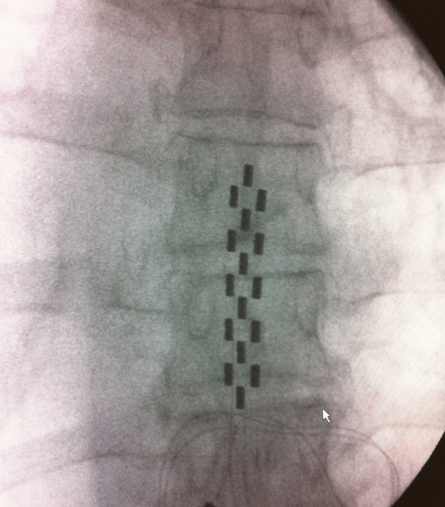

Phase de test avec une électrode chirurgicale pour soulager des douleurs chroniques post-chirurgicales

L’électrode sera implantée de manière percutanée (sous anesthésie locale, le patient éveillé) ou bien chirurgicalement (sous anesthésie générale) à la surface de la dure-mére.